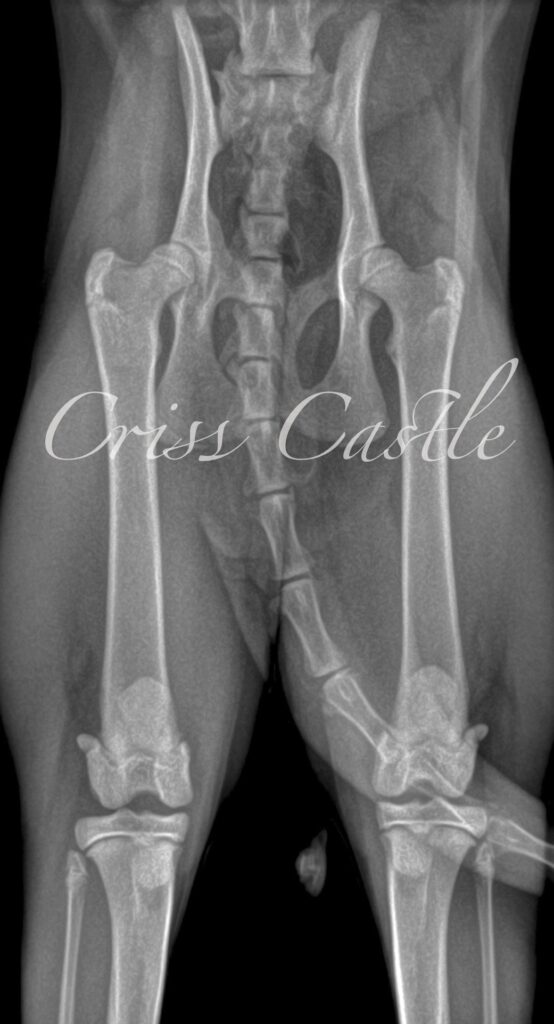

Hip X-Ray Results

Below are the current hip x-ray results for each Criss Castle breeding cat.

Note that as the cats continue to grow, this page may be updated with new results.